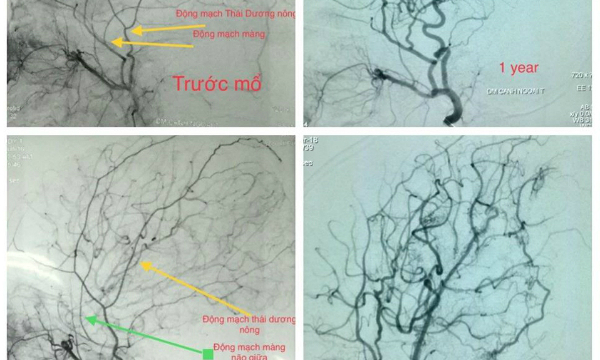

– Khảo sát hình ảnh bệnh nhân mắc Moyamoya trước và sau phẫu thuật. Phụ nữ có khả năng mắc bệnh này cao gấp đôi. Độ tuổi phổ biến cho trẻ em là 5 đến 9 tuổi. Hầu hết bệnh nhân nhi được đưa vào bệnh viện vì nhồi máu não hoặc cơn thiếu máu não thoáng qua. Ở trẻ em, bệnh thường bắt đầu sau khi gắng sức. Ở trẻ nhỏ, ăn uống, lo lắng hoặc ho cũng có thể gây thiếu máu não hoặc đột quỵ. Các triệu chứng khác bao gồm đau đầu, chóng mặt và co giật … Do bệnh phát triển nhanh, nhu cầu cung cấp máu của não ngày càng không đủ. Nếu không được điều trị kịp thời, nhiều cơn đột quỵ có thể xảy ra. Với mỗi cơn đột quỵ, não sẽ bị tổn thương không thể phục hồi, dẫn đến khiếm khuyết, di chứng thần kinh và thậm chí tử vong. Đứa trẻ được đánh giá, các mạch máu trong não được kiểm tra, và sau đó phẫu thuật được thực hiện để cung cấp một nguồn cung cấp máu mới cho não. Theo dõi cho thấy sau khi phẫu thuật, nhiều trẻ em không còn bị thiếu máu cục bộ và kiểm tra lại hệ thống mạch máu não để thấy một kết nối tốt từ bên ngoài đến não và cung cấp máu cho não. Trong một số trường hợp, do điều trị muộn, thiệt hại do đột quỵ trước đó nghiêm trọng đến mức vẫn sẽ có hậu quả về thần kinh sau phẫu thuật.